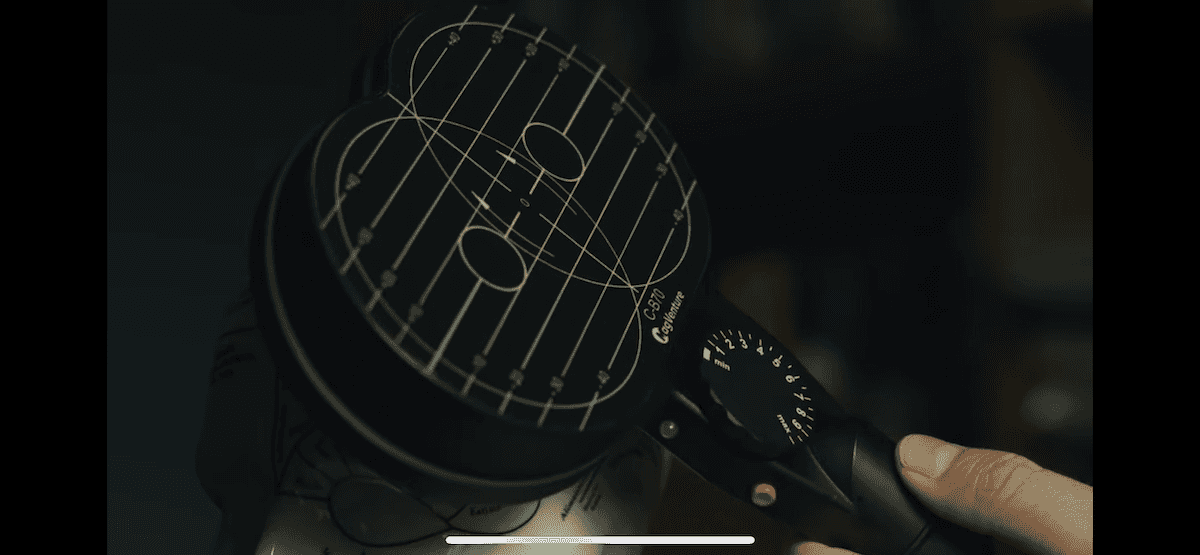

TMS does not require surgery or medication; it works externally by using magnetic stimulation to target specific areas of the brain. It is a non-invasive and well-tolerated method.

TMS can be used to target specific brain regions, such as the prefrontal cortex, without affecting the entire body.

A session lasts around 20–40 minutes and does not require a recovery period — patients can immediately return to work or other responsibilities.

Unlike electroconvulsive therapy (ECT), transcranial magnetic stimulation (TMS) does not require hospitalisation or general anaesthesia, nor is there any recovery period necessary following the procedure. After TMS session the patient can follow directly with daily activities. TMS is a non-invasive, safe, and well-tolerated treatment. It does not cause cardiovascular or respiratory complications, nor cognitive side effects — which may occur with ECT.

The two methods also differ in their mechanisms of action: TMS uses magnetic pulses to gradually and precisely modulate activity in targeted areas of the brain, while ECT induces seizures using electrical currents.